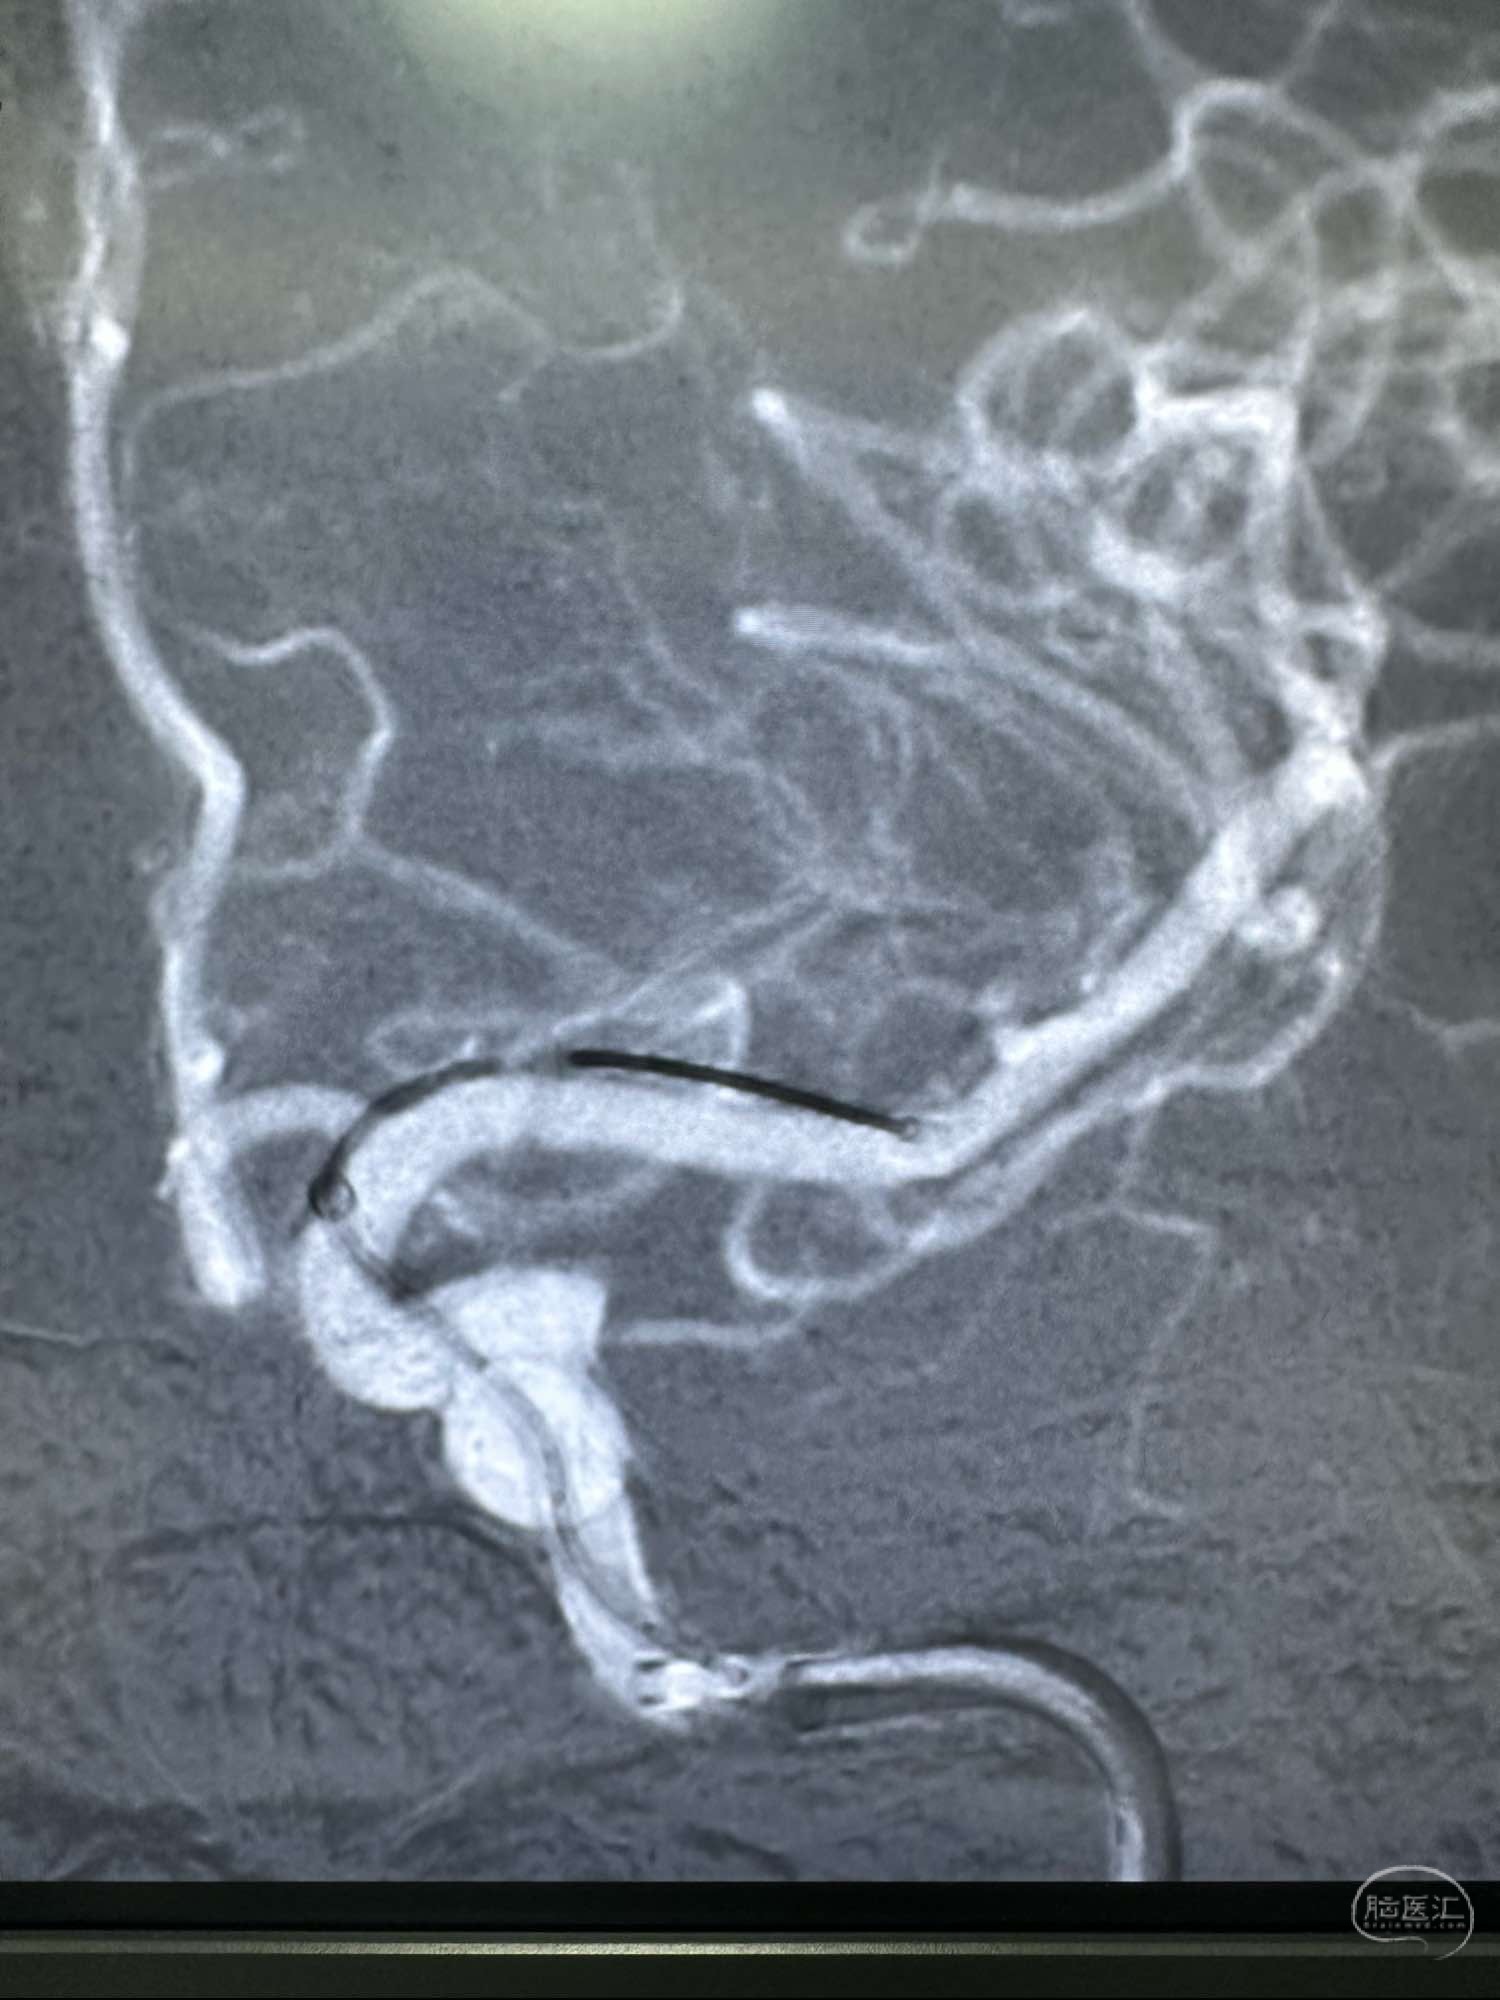

另外一个角度